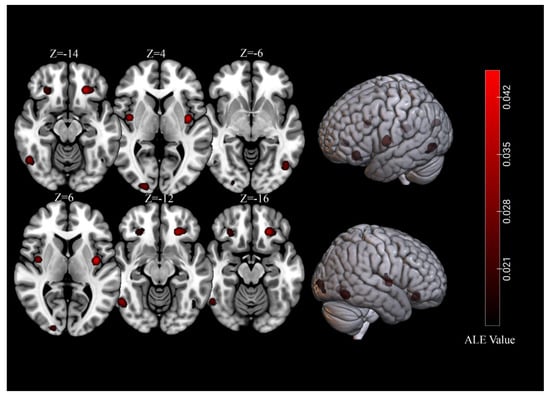

| Cluster | Cluster Size (mm3) | Brain Region | Peak Voxel MNI Coordinates | ALE Value (×10−2) | Z | Contributing Samples | |||

|---|---|---|---|---|---|---|---|---|---|

| X | Y | Z | No. | % | |||||

| 1 | 4096 | L Lingual Gyrus | −14 | −98 | −4 | 3.65 | 5.28 | 20 | 29% |

| 2 | 3680 | L Orbitofrontal Cortex | −26 | 34 | −14 | 6.94 | 8.40 | 21 | 31% |

| 3 | 3368 | R Lingual Gyrus | 22 | −90 | −8 | 2.88 | 4.43 | 18 | 26% |

| 4 | 3232 | R Amygdala | 28 | −6 | −20 | 2.30 | 3.71 | 17 | 25% |

| 5 | 3136 | R Fusiform Gyrus | 38 | −76 | −16 | 2.29 | 3.69 | 16 | 24% |

| 6 | 3040 | L Fusiform Gyrus | −30 | −78 | −12 | 2.63 | 4.13 | 18 | 26% |

| 7 | 2512 | R Orbitofrontal Cortex | 26 | 32 | −14 | 4.35 | 6.01 | 15 | 22% |

| 8 | 2312 | L Insula | −38 | −6 | 6 | 6.90 | 8.36 | 16 | 24% |

| 9 | 2184 | L Amygdala | −20 | −6 | −18 | 3.94 | 5.59 | 13 | 19% |

| 10 | 2168 | R Middle Occipital Gyrus | 36 | −84 | 12 | 4.31 | 5.98 | 11 | 16% |

| 11 | 1376 | L Culmen | −32 | −56 | −18 | 3.27 | 4.87 | 7 | 10% |

| 12 | 1352 | R Insula | 40 | −4 | 4 | 5.46 | 7.09 | 10 | 15% |

| 13 | 1176 | R Inferior Frontal Gyrus | 46 | 6 | 26 | 3.41 | 5.03 | 6 | 9% |